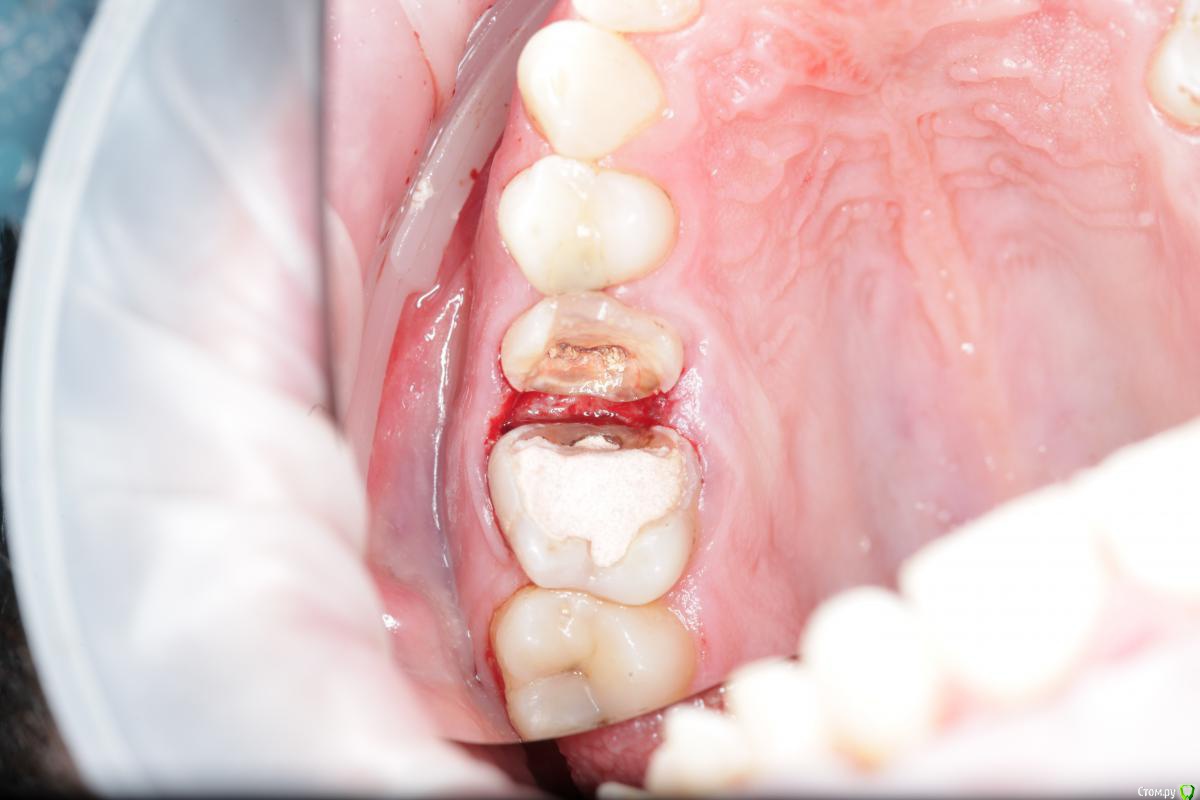

Карен Аванесов Опубликовано 10 апреля, 2016 Поделиться Опубликовано 10 апреля, 2016 Уважаемые коллеги, тут вот поймал себя на мысли, что не знаю как бескровно в данной ситуации сделать изоляцию при помощи коффердама. Давным-давно, без хирургии приходилось долго мучиться, с хирургией, порой очень деликатной, такое решается за считанные минуты. Наверняка не все делают хирургическое удлинение, но как тогда, расскажите (покажите при возможности фото) пожалуйста каким образом при таких дефектах, вы бескровно делаете надежную изоляцию и сколько времени на это тратите? Хочется иметь и наличие в запасе быстрых бескровных вариантов. Спасибо. 1 Ссылка на комментарий

Гарриевич Опубликовано 10 апреля, 2016 Поделиться Опубликовано 10 апреля, 2016 (изменено) Карен, чем десну порезали?По вопросу: платок по жёстче, флоссом подвязаться, фумкой запихнуть Потом фумкой можно убрать Изменено 10 апреля, 2016 пользователем Гарриевич Ссылка на комментарий

Каплан Опубликовано 11 апреля, 2016 Поделиться Опубликовано 11 апреля, 2016 1. платки хэви2. бить дырки по шаблону СтайлИтальяно или по тому который я выкладывал в фейсбуке или в блоге. 3. не лениться и тянуть хотя бы до премоляров. а лучше до резцов. тогда не надо будет медаильно кламп. 4. в данном случае еще усложняет ситуацию тот факт, что сосочки остальсь только орально и вестибулярно. они то и дают натяжение, а между ними провал. поэтому берем лысый шарик на ножке (до металла лысый), или коагулятор. и слегка по вершинам. совсем чуть чуть. при правильно создании контактного пункта они восстановятся. 3 Ссылка на комментарий

M@estro Опубликовано 11 апреля, 2016 Поделиться Опубликовано 11 апреля, 2016 (изменено) Кламп в таких случаях я ставлю на разрушенный зуб в любом случае, даже если до премоляра тяну. В конкретном кейсе вопрос в расстоянии между дырками - они слишком "с запасом". Получились не стринги, а "семейки" ) В остальном все написали, тефлон решает, но при избытке платка будет проблема. Так или иначе, в не зависимотси от шаблона , дырки все равно пробиваются по ситуации ( скученность, ротированный зуб и т.д) Изменено 11 апреля, 2016 пользователем M@estro 4 Ссылка на комментарий